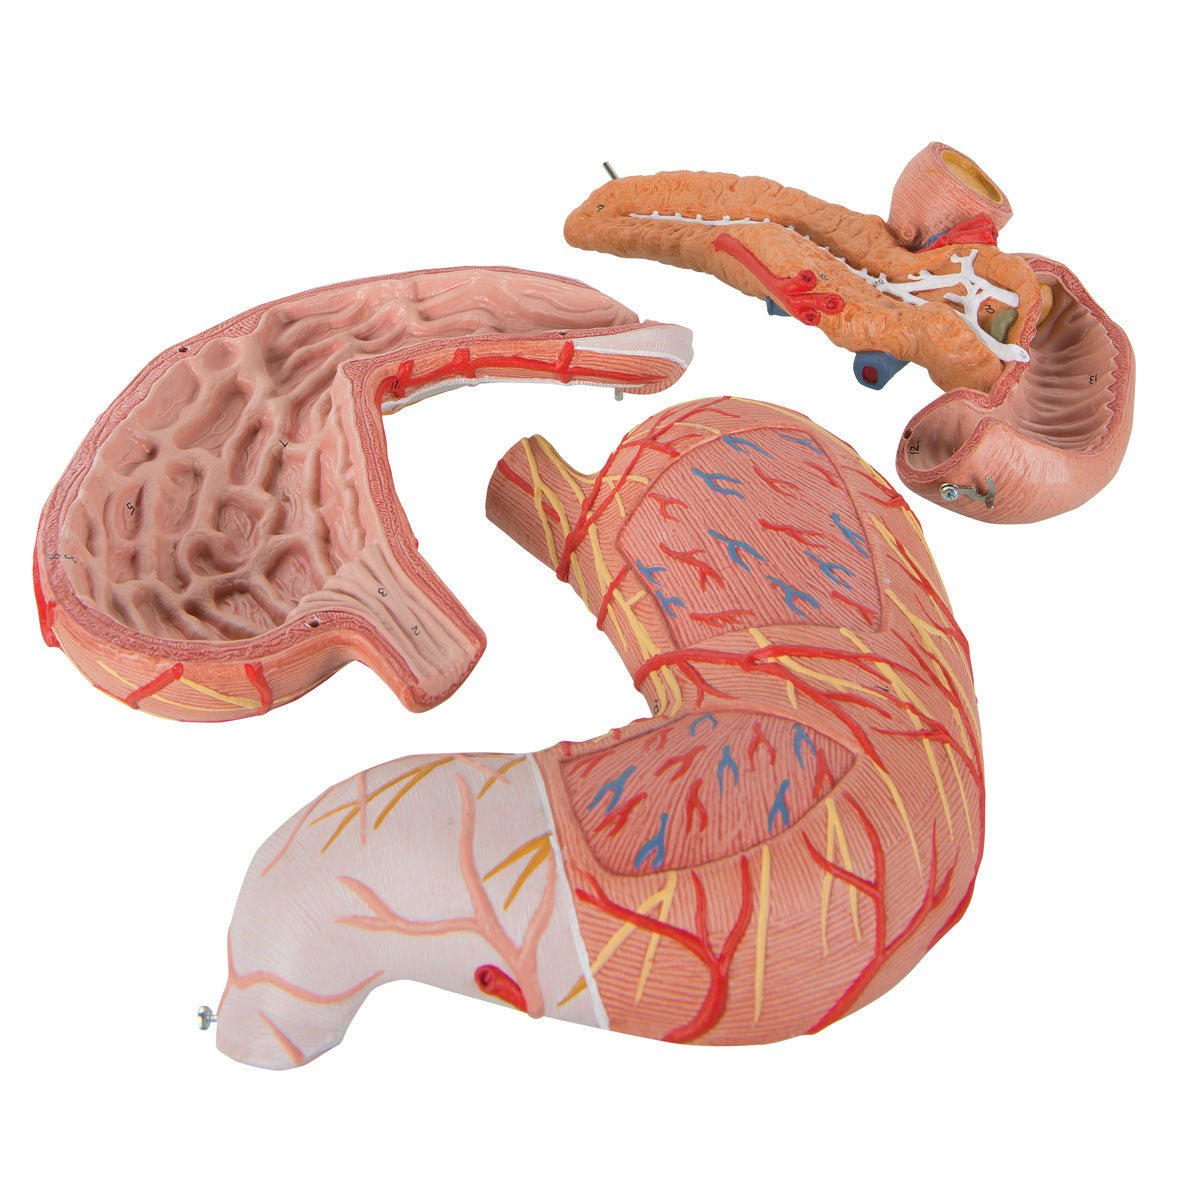

Salg af anatomiske modeller er det bærende element i eAnatomi, selvom vi også bruger mange ressourcer på at udvikle vores egne anatomiske materialer som fx plakater. Anatomiske modeller anvendes til forskellige formål og kan både vise afgrænset væv, organer samt organsystemer. Søger du en simpel model af knoglevæv eller måske en avanceret torso-model baseret på MRI teknologi, kan du finde det hele på eanatomi.com.